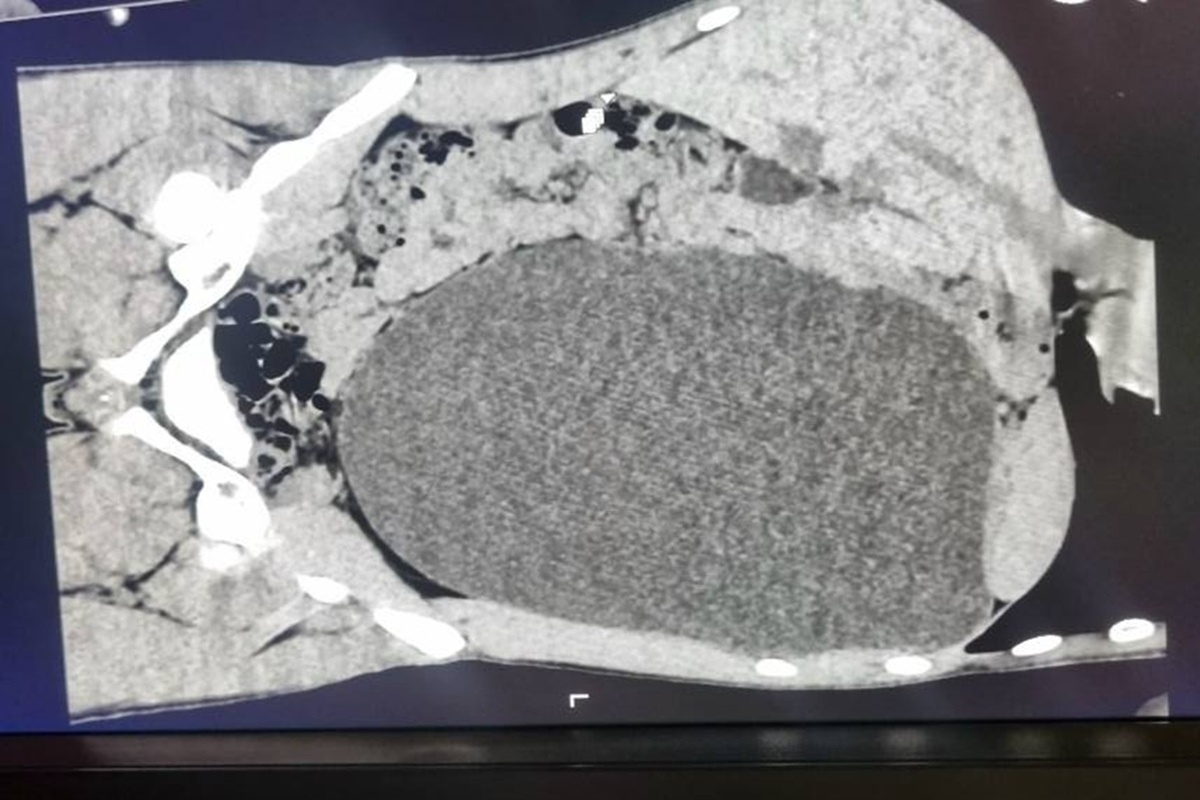

17-летний житель Новосибирска пришел устраиваться на работу, прошел УЗИ и случайно узнал о смертельной опасности. Оказалось, что его почка раздулась до невероятных размеров и давила на все внутренние органы. Плановый медосмотр перед устройством на работу спас жизнь 17-летнему новосибирцу. Во время УЗИ врачи обнаружили у юноши огромное образование в брюшной полости. Как выяснилось позже, это была левая почка, пораженная гидронефрозом — она раздулась до размеров пятилитровой бутыли и почти полностью утратила функциональную ткань. «У нашего пациента почка достигла размеров пятилитровой бутылки! Она занимала почти весь объем живота и давила на все соседние органы. Это была настоящая "бомба замедленного действия": любая травма, случайный удар в живот — и мешок мог разорваться внутри», — рассказали в детской горбольнице №1. Детский хирург-уролог Ирина Живолуп пояснила: парень поступил из амбулаторного звена после случайной находки. Гидронефроз часто протекает бессимптомно, и если бы не профо

Плановый медосмотр перед устройством на работу спас жизнь 17-летнему новосибирцу. Во время УЗИ врачи обнаружили у юноши огромное образование в брюшной полости. Как выяснилось позже, это была левая почка, пораженная гидронефрозом — она раздулась до размеров пятилитровой бутыли и почти полностью утратила функциональную ткань.

«У нашего пациента почка достигла размеров пятилитровой бутылки! Она занимала почти весь объем живота и давила на все соседние органы. Это была настоящая "бомба замедленного действия": любая травма, случайный удар в живот — и мешок мог разорваться внутри», — рассказали в детской горбольнице №1.

Фото: Минздрав Новосибирской области, источник t.me zdravnso